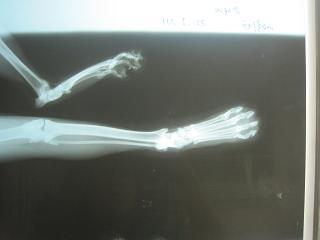

主題: 動保處保出的虎斑貓 申請者姓名: 岳丹楓 花色: 申請日期: 2012-07-08 18:10:23 申請者部落格: 申請者臉書網址: 所在縣市/合作醫院: 台北市/詠欣動物醫院 治療費用: 8200元 需求人數: 20人 已結案 (2012-12-01 21:44:33) 報名人員: yiwith(已付款)、juno(已付款)、蘇威倫(已付款)、Shirley(已付款)、Mjay(已付款)、Yiling Tsai(已付款)、Liyun Chang(已付款)、小可(已付款)、小節(已付款)、小節(已付款)、潘逸群(已付款)、迷迷(已付款)、Cloudy Wu(已付款)、H.l. Lai(已付款)、Chiu-Hui Lee(已付款)、陳比比(已付款)、Huang Guo Hua(已付款)、Roxy Chen(已付款)、阿豪(已付款)、莎拉拉(已付款)、 候補人員: 小舟、小舟、 動物病情說明: 這隻貓咪是在吳興街284巷中 抓到動保處的.保回時,左後腳有蜂窩性組織炎.有點脫水,遂住院治療.照X光,骨頭沒有骨折.治療13天後,有順道結紮.之後就放回原地.